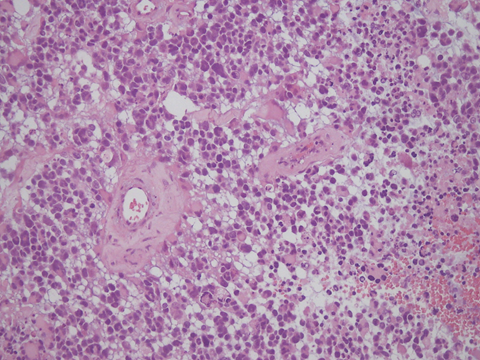

圖1. 惡性腦瘤擴散程度迅速又難以根除,且手術後容易復發。